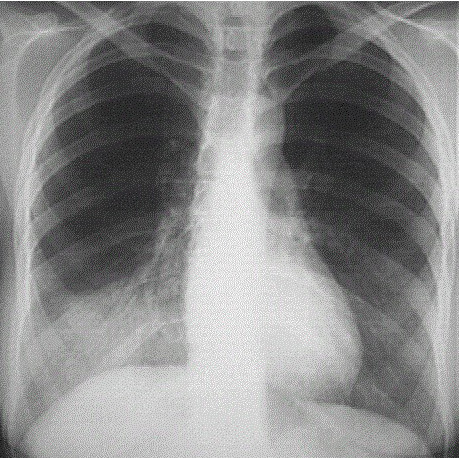

La prise en charge d’une pneumopathie communautaire du sujet jeune se fait en ambulatoire. Seule une radiographie thoracique est recommandée dans le bilan de première intention.